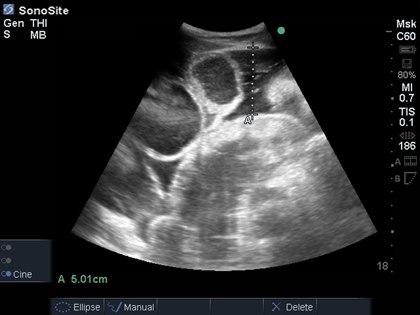

EQUINE ABDOMINAL ULTRASONOGRAPHY - WHAT WE CAN LEARN

The use for ultrasound imaging in equine studies allows non-invasive examination in animals that are conscious, bypassing the need for sedation which could otherwise be problematic